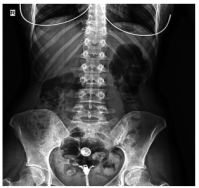

Dose reduction was used in patients with moderate and severe back pain, constituting 37.2% of the patients describing the complaint. The vast majority of these patients responded to dose reduction, while eight (10.2%) patients needed to use non-steroidal anti-inflammatory drugs for pain relief. Sacroiliitis was present in four (4%) patients, including three females and one male. There was no statistically significant difference between the sexes for sacroiliitis development (p=0.25). Bilateral sacroiliitis was detected in one patient (Figure 1). Sacroiliitis regressed 1.5 to 2.5 months after isotretinoin treatment cessation in all patients. The patients diagnosed with sacroiliitis were followed for six months. Three (3%) patients described myalgia, which was of mild severity and did not require additional treatment. Among these patients, two female patients also described low back pain. Creatine kinase (CK) elevation was observed in 18 (18.1%) patients, including 13 males and two females, one to three months after the beginning of treatment (p=0.1). The elevated CK values ranged between 233 and 940 IU and returned to normal levels after dose reduction. One (1%) female patients who was on low-dose isotretinoin treatment (0.5 mg/kg) was diagnosed with enthesitis at three months of treatment (Figure 2).